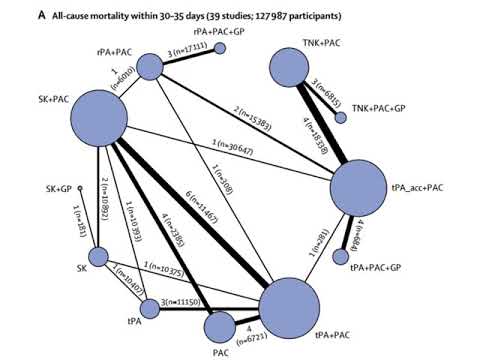

Comparación de la eficacia y seguridad de la reperfusión con fibrinolíticos. Dr. Pablo Rivara. Residencia de Cardiología. Hospital C. Argerich. Buenos Aires